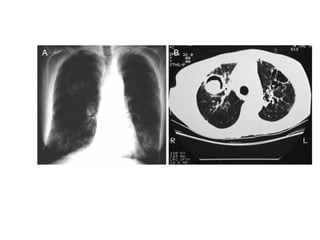

Question 10 44yo with 3 week h/o fever, purulent cough and wt loss SZ d/o s/p seizure 1 month ago CXR with 2.5cm cavity in superior segment RLL with A/F level (+) ppd

What is the most appropriate therapeutic step? A.  Culture sputum for anaerobic bacteria and begin treatment with clindamycin B.  Send sputum for AFB stain and culture and begin treatment with INH, RIF, PZA and ETB C.  Begin treatment with metronidazole and schedule bronchoscopy Send sputum for gram stain and AFB and treat empirically with piperacillin/tazobactam

Question 10 Send sputum for gram stain and AFD and treat empirically with piperacillin/tazobactam  Identify the clinical presentation of a lung abscess and select appropriate therapy.

Question 10 44yowith 3 week h/o fever, purulent cough and wt loss SZ d/o s/p seizure 1 month ago CXR with 2.5cm cavity in superior segment RLL with A/F level (+) ppd

What is themost appropriate therapeutic step? A. Culture sputum for anaerobic bacteria and begin treatment with clindamycin B. Send sputum for AFB stain and culture and begin treatment with INH, RIF, PZA and ETB C. Begin treatment with metronidazole and schedule bronchoscopy Send sputum for gram stain and AFB and treat empirically with piperacillin/tazobactam

Question 10 Sendsputum for gram stain and AFD and treat empirically with piperacillin/tazobactam Identify the clinical presentation of a lung abscess and select appropriate therapy.